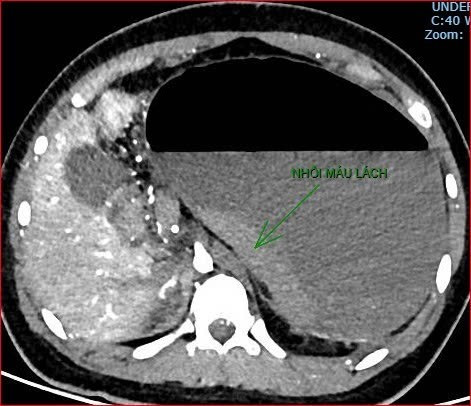

Khoảng 21 giờ 40 phút, kết quả chụp cắt lớp vi tính cho thấy tình trạng bệnh rất nặng và hiếm gặp, gồm: xoắn dạ dày, nhồi máu thận trái, nhồi máu lách, viêm đầu tụy, viêm hỗng tràng kèm dịch ổ bụng và tràn dịch màng phổi, trên nền bệnh nhân có hội chứng Down và tim bẩm sinh.

Hình ảnh chụp cắt lớp vi tính thể hiện tình trạng bệnh nhân rất nặng, hiếm gặp.